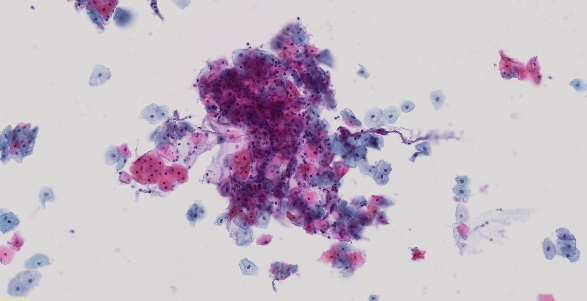

清晰捕捉细胞学样品的图像

SLIDEVIEW VS-M1

其他领军品牌